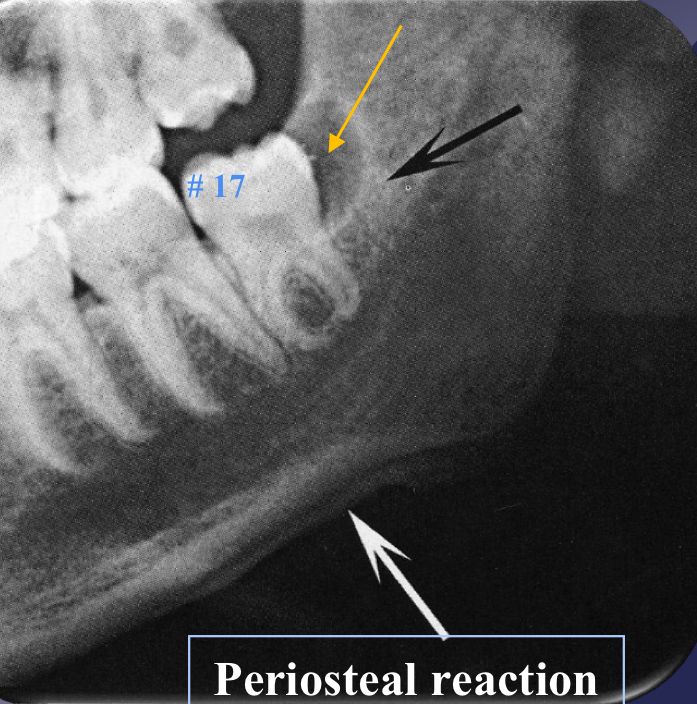

which osteomyelitis phase?

some effects on surrounding structures:

bone formation, periosteal stimulation = onion skin

bone resorption

acute

periosteal reaction

new bone formation parallel to the cortex (almost looks like periosteum lifted and bone under)

proliferative periostitis and the onion skin periosteal reaction have the same radiographic appearance

true